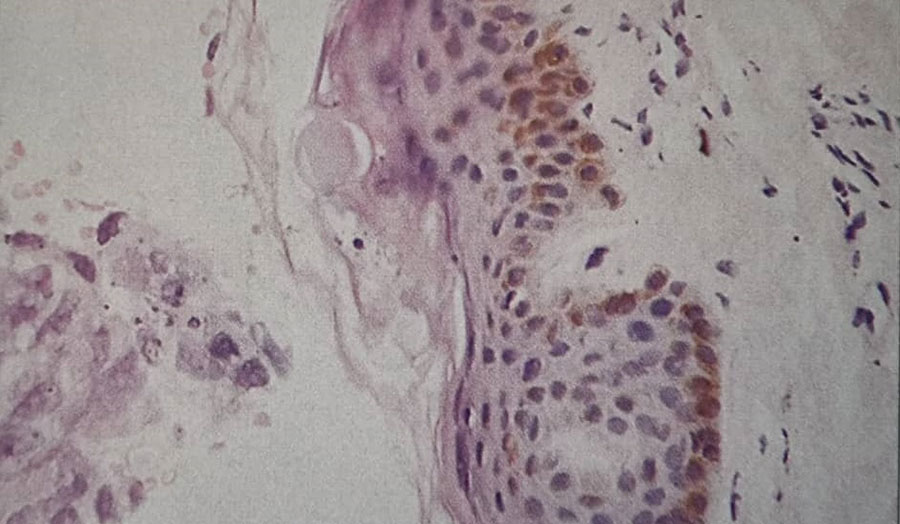

2. نظر شما در مورد آسپیراسیون مغز استخوان (شکل 63b) و بیوپسی ترفین (شکل 63c) چیست؟

آسپیراسیون و بیوپسی ترفین مغز استخوان نشاندهنده نفوذ سلولهای غیرطبیعی هستند؛ عناصر غدهای (glandular elements) بهوضوح در بیوپسی ترفین دیده میشوند. این نما با کارسینوم ثانویه (متاستاتیک) سازگار است. بیمار همچنین دچار کمردرد میباشد.

همچنین سلولهایی از کارسینوم معده در یک آسپیراسیون مغز استخوان (شکل 63d) و بیوپسی ترفین کارسینوم سلول اوت (Oat cell carcinoma) برونش در تصویر دیگری نشان داده شدهاند . (شکل 63e)